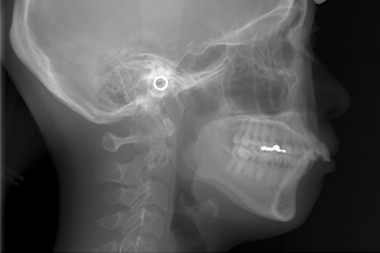

セファロ分析

歯科専用のレントゲンです。矯正治療において分析の根本となるもので、セファロ分析を行うことで口腔内の不正歯列が明らかになります。歯の角度や距離を計測することで、歯の移動の仕方や抜歯の有無などについての判断材料としても有効です。セファロ分析の結果、マウスピース型矯正歯科装置による歯列矯正に向いていない場合もあるので治療を成功させるためにも重要な検査といえます。

セファロ分析により不正歯列を確認

正常な歯列のセファロ分析

正常な歯列

上顎前突のセファロ分析

上顎前突の場合

下顎前突のセファロ分析

下顎前突の場合